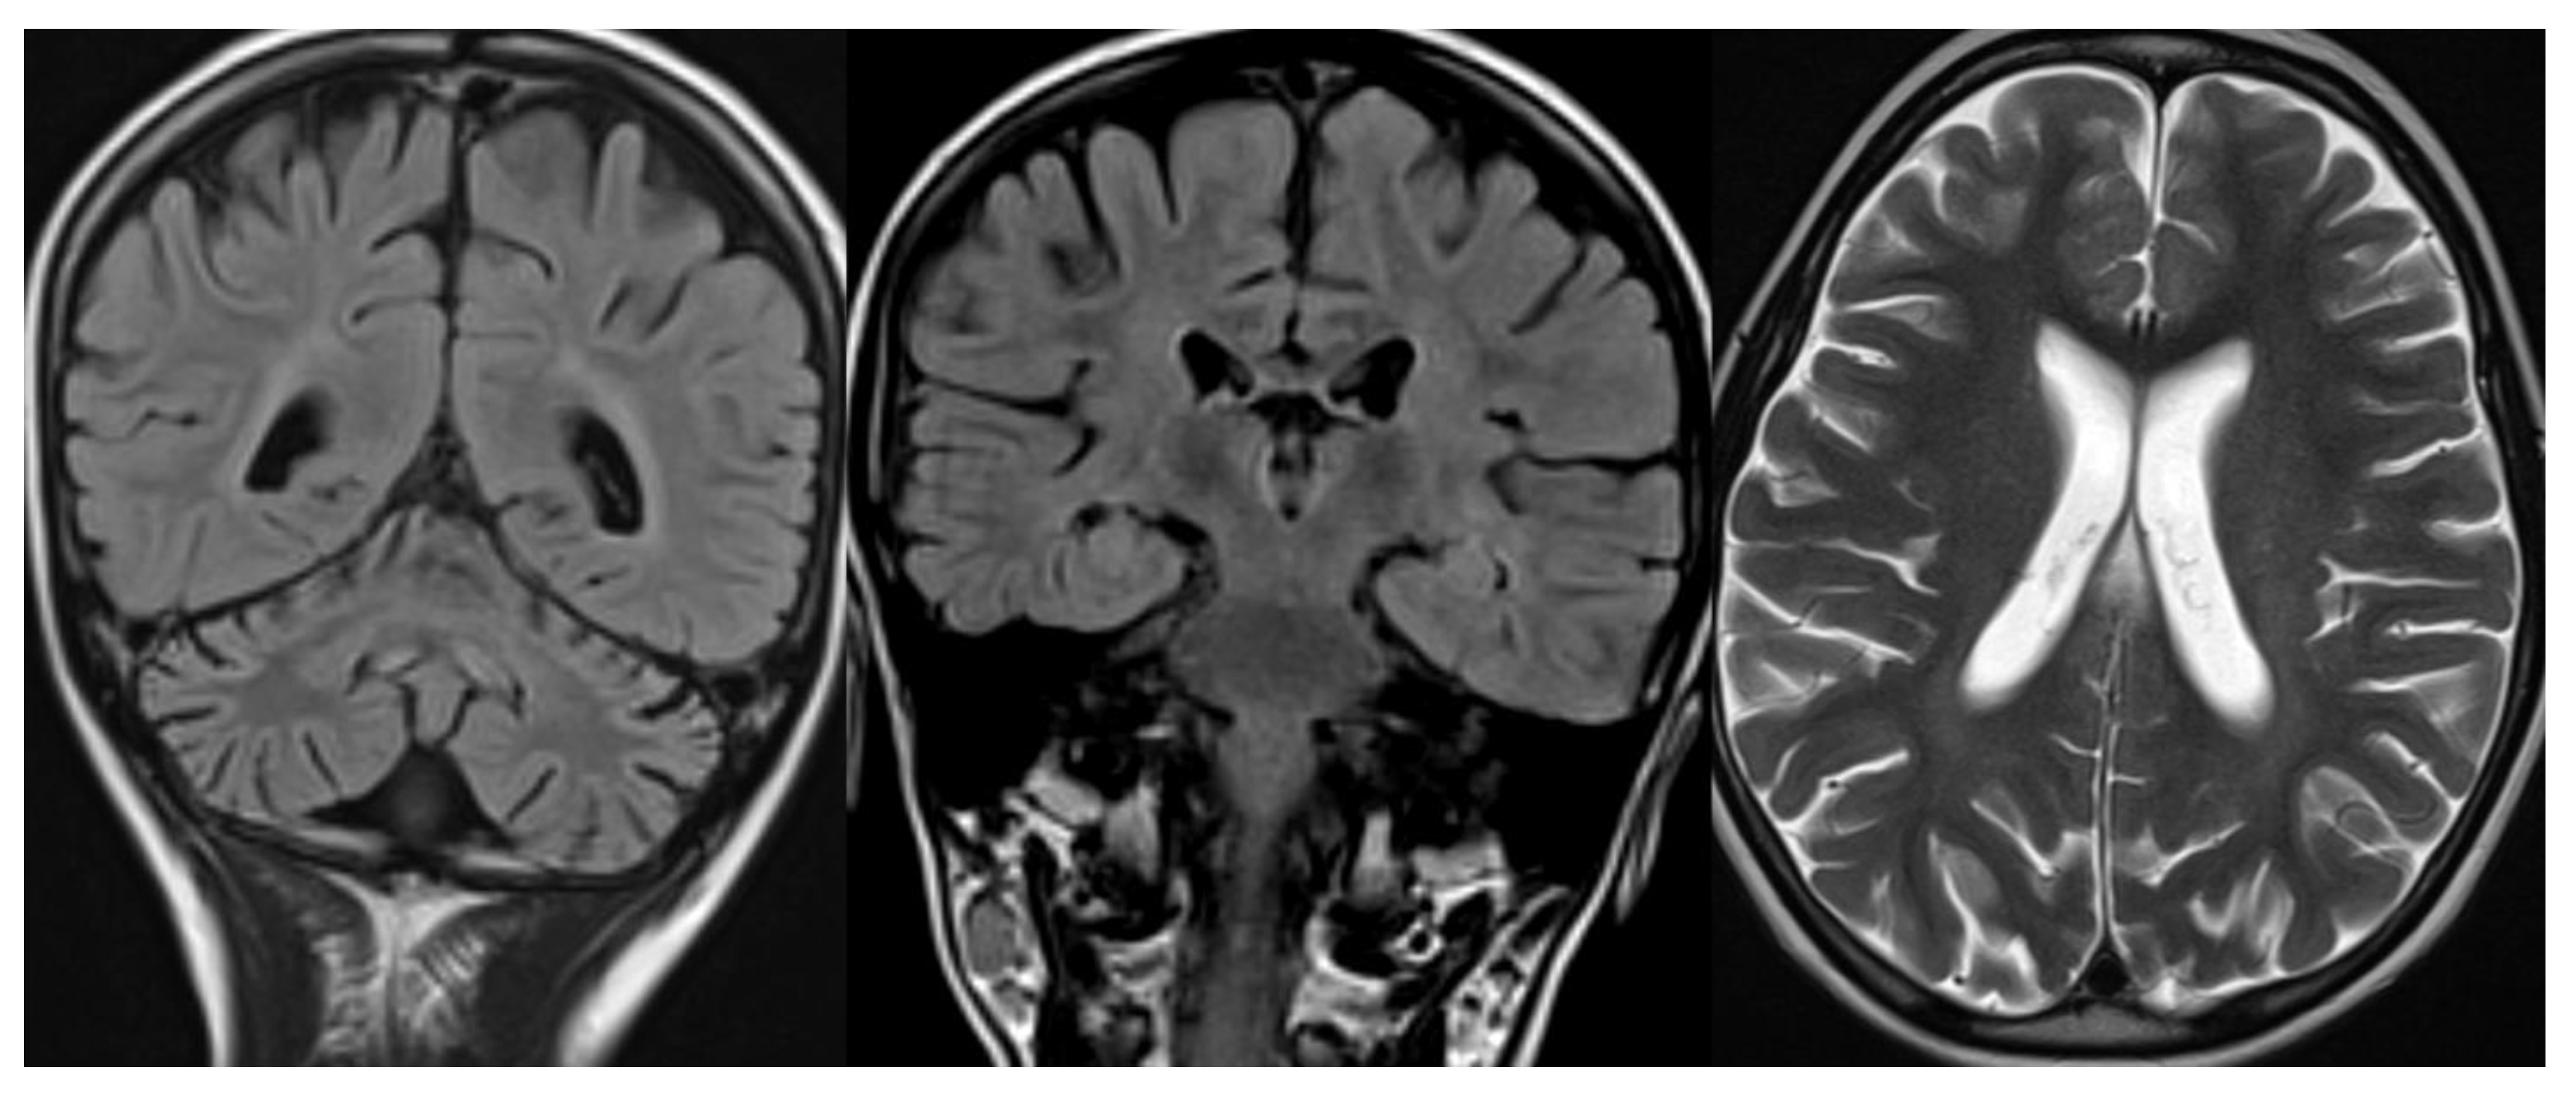

The neuroradiological findings in the different forms of NCL are quite similar: thalamic involvement with T2 hypointensity fading away with increasing age of onset; infra and supratentorial atrophy with distinct thinning of the cerebral cortex, and white matter T2 hyperintensity, usually not marked, with appearance only in adolescence and juvenile forms [30] (Figure 6).

Figure 6.

Infantile NCL (CLN6). Brain MRI scan of a 6-year-old girl. MR images demonstrate diffuse cerebellar and cerebral atrophy associated with the markedly decreased signal intensity of the thalami. The last image shows hyperintensity in the deep and periventricular white matter.